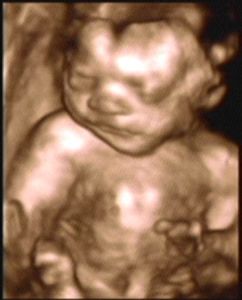

3D/4D SONOGRAPHY 18-24 WEEKS

- From a continuous 3D acquisition you get a live action view. It is known as 4D where 4th dimension is time.

- Improved maternal -fetal bonding.